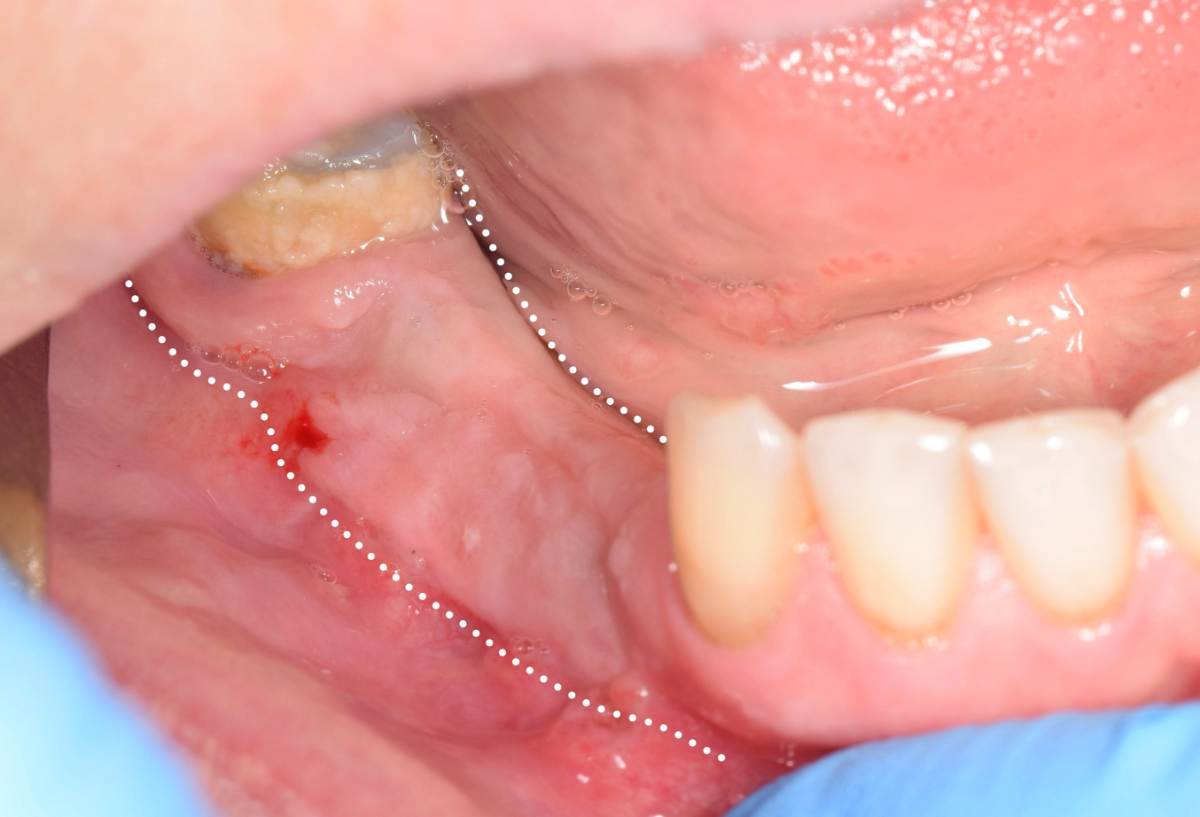

Fin Опубликовано 5 июня, 2025 Поделиться Опубликовано 5 июня, 2025 Здравствуйте коллеги. Хотел бы представить вашему вниманию первую часть кейса по восстановлению 4 сегмента. Перелом зуба 4.5 под мостовидным протезом 4.7-4.4. 4.7 решено оставить до последующего повторного протезирования При планировании имплантации вестибулярное оголение имплантата на 1.5-2мм в области 3. 4. Дефицит керотинизированной слизистой оболочки. Более глубокое положение имплантата приведет к чрезмерному количеству сзизистой оболочки в 7-8 мм. Решено не пытаться использовать ССТ с целью перекрытия оголенного имплантата а попробовать технику морковки профессора Кюри. 1 этап операции. Удаление зуба 4.5, подготовка костного ложа под имплантаты при помощи трепанов и запор костных морковок, установка имплантатов неодент 3.75х10 в позицию 4.4, 4.3х10 в позицию 4.6, ушивание. 2 этап. Создание прикрепленной слизистой. Расщепление лоскута, удаление пиноа, пересадка СДТ с фиксаций его этими же пинами. 3 этап. Открытие имплантатов с установкой ФДМ и снятие швов через 2 недели. Решил не добавлять ССТ. На данный момент ожидаем полное восстановление тканей и приступаем к этапу протезирования. Так как параллельность имплантов достаточна планирую протезировать с уровня имплантатов. 3 2 1 Ссылка на комментарий